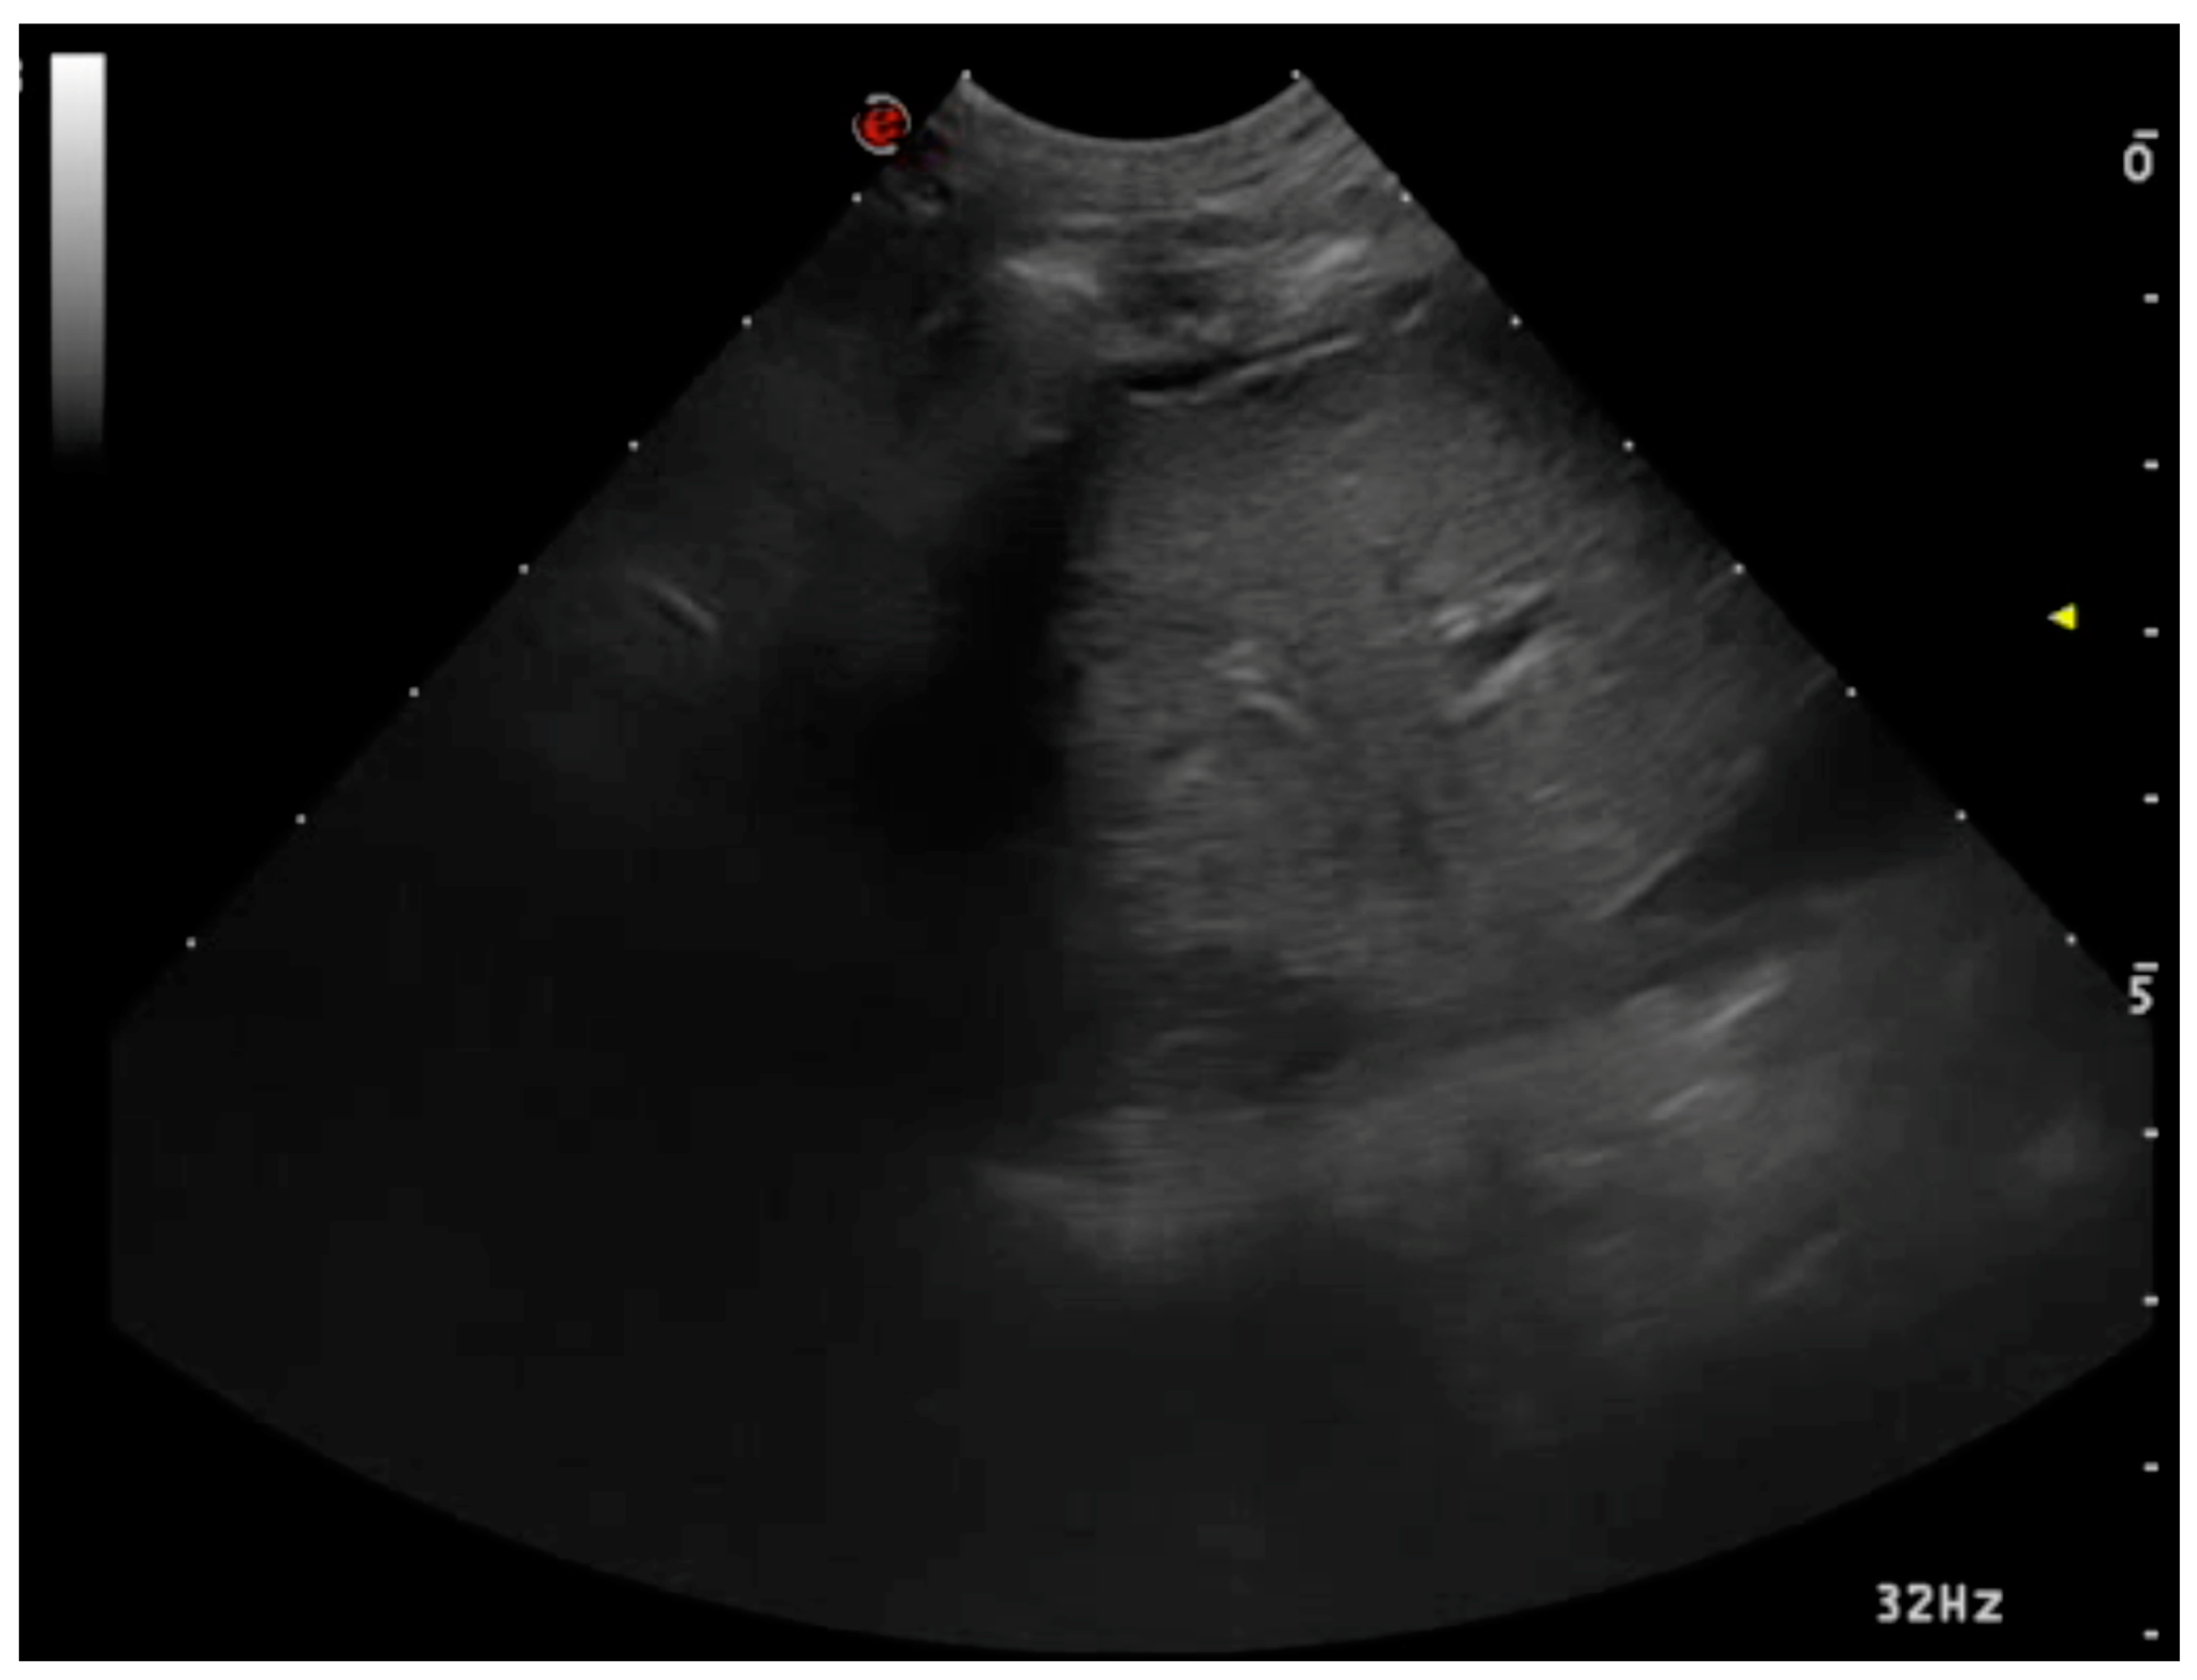

3.2.2. Cardiogenic Pulmonary Edema